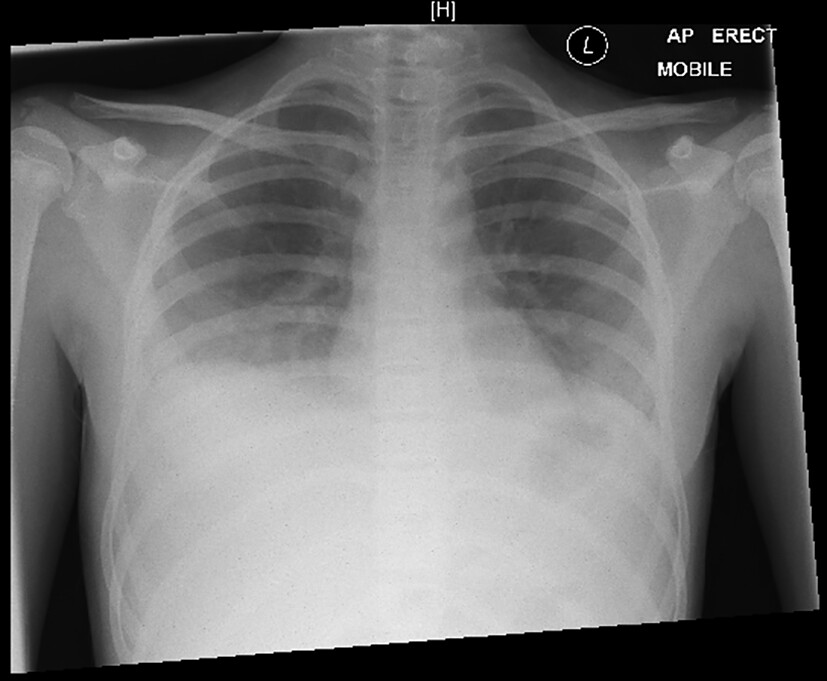

Umgehend erfolgt die Anlage eines Peritonealkatheters, um eine kontinuierliche Peritonealdialyse beginnen zu können. Die Flüssigkeitszufuhr wird beschränkt auf 400 ml/m² KOF/Tag („insensible losses“). Noch am Aufnahmeabend beklagt das Mädchen zunehmende Kopfschmerzen und Doppelbilder. Sie erscheint deutlich verwirrt und wesensgeändert. Die übrige neurologische Untersuchung und das EEG sind unauffällig. Die kranielle MR-Tomographie zeigt eine nahezu symmetrische Diffusionseinschränkung in den Basalganglien, aber keine offensichtlichen T2-Hyperintensitäten, außer im dorsalen Thalamus. Zudem sind diskrete Diffusionseinschränkungen im präzentralen Cortex erkennbar. Infratentoriell bestehen ebenfalls fast symmetrische punktförmige T2-Hyperintensitäten im dorsalen parazentralen Pons, in der Medulla oblongata und im Lobus flocculonodularis (Abb. 2). Hier ist keine Diffusionseinschränkung erkennbar. Hinweise für Blutungen, auch Mikrohämorrhagien, gibt es nicht, kein Hirnödem, unauffällige Liquorräume. Die Gefäßdarstellung und Perfusion sind unauffällig.